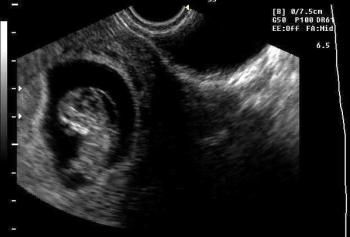

CC is a 31 year old primigravida who was referred for ultrasound at a community hospital due to suspected cardiac anomalies noted on a screening sonogram at her doctor's office. Due to concern about a probable cardiac abnormality an amniocentesis was performed at the local hospital.